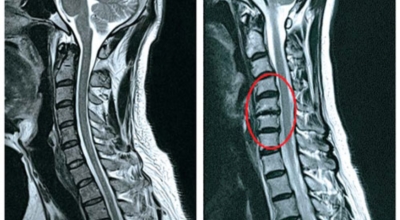

목디스크가 심한 경우에는 어깨뿐만 아니라 팔과 손가락에도 저림을 동반한 고통을 느끼실 수 있어요. 디스크의 수핵이 빠져나가거나 퇴행성 경추 척추증 및 경추관협착증 등으로 척수가 눌리게되면 대개는 팔의 힘이 빠지는 느낌을 받을 수 있어요. 이러한 경우에는 팔을 머리 위로 들면 고통이 완화되는 경우가 있는데 일시적일 뿐 목디스크의 전형적인 증상이니 꼭 정형외과에 내원하셔서 의사에게 상담을 받아보시길 권장드려요.

목디스크 증상이 나타날때 빨리 발견하여 비수술 치료를 받고 꾸준히 관리하는 것이 베스트이죠. 목디스크 환자 중 수술을 진행하는 환자는 2% 미만으로 현저히 적다고 해요. 수술을 진행하는 경우는 감각이 느껴지지 않는 마미증후군이나, 한쪽 다리가 눈에 띌 정도로 야윈 경우에만 진행하므로 올바른 자세 교정만으로도 충분히 호전될 수 있는 질병이죠. 목에 연관된 검사는 MRI나 CT를 이용해요. 그러나 전자의 경우 비용이 굉장히 비싸기 때문에 디스크 증세가 확실하다고 생각될 경우에만 선택적으로 하고 의무적으로 하는 건 아니니까 비용에 대해선 부담을 가지지 마시길 바래요.

목디스크 증상으로 인해 3개월 이상 약물이나 물리치료를 해도 효과가 없을 경우 수술을 고려해야 해요. 통증이 심해서 일상생활에 지장이 있거나, 신경증상이 악화되고 근력도 함께 줄어들 때와 큰 디스크가 탈출해 중추신경인 척수를 압박해 척수증이 발생하는 경우에도 수술을 고려할 수 있어요.

수술할 때는 목의 앞쪽에서 디스크를 완전히 제거한 뒤, 뼈를 이식을 하는 방법을 가장 보편적으로 사용하는 편이예요. 디스크가 세 곳 이상인 경우 목의 뒤쪽에서 수술하는 방법이 효과적이며, 수술 후에는 보통 6주에서 3개월 정도 목보조기를 착용하는 것이 좋아요.